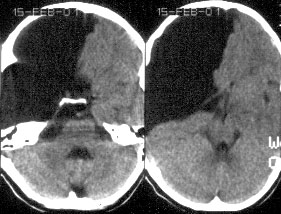

CHIARI-1 – характеризуется опущением миндаликов мозжечка ниже уровня большого затылочного отверстия, что часто сопровождается формированием сирингомиелии на шейно-грудном уровне.

Диагностика: На настоящий момент МРТ головного мозга является методом выбора при диагностике данной патологии. Следует отметить, что кроме МРТ головного мозга при подозрении на аномалию Киари-1 необходимо сделать МРТ шейного и грудного отделов спинного мозга для исключения/подтверждения сирингомиелии. И, наоборот, при наличии сирингомиелии в обязательном порядке необходимо сделать МРТ головного мозга с особым вниманием на состояние структур ЗЧЯ.

CHIARI-2 – часто сопутствует миеломенингоцеле. При этом патологическом состоянии отмечается еще большее опущение миндаликов мозжечка (они обычно находятся вне полости черепа), каудальная дислокация структур ЗЧЯ – т.е. ствол, 4-й желудочек расположены значительно ниже, частично или полностью в спинномозговом канале, а каудальные черепно-мозговые нервы имеют восходящее направление (в отличие от “нисходящего” в норме).

Диагностика: МРТ является методом выбора. Кроме дистопии структур ЗЧЯ часто встречаются различные другие аномалии развития головного мозга, гидроцефалия (значительно чаще, чем при Киари-1). Ларингоскопия – помогает оценить степень нарушения иннервации глотки и гортани.